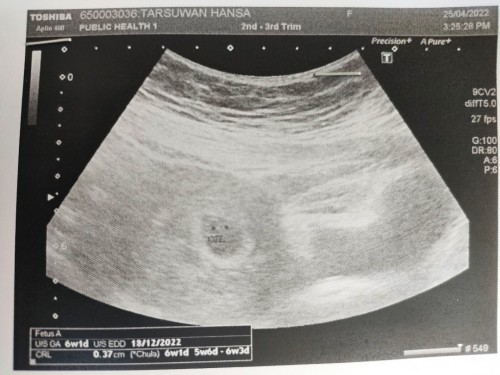

ฝากครรภ์6w1d

วันนี้เพิ่งไปฝากครรภ์มาค่ะ หมอusบอกว่าตอนนี้น้องกำลังสร้างหัวใจอยู่เป็นจุดเล็กๆ หัวใจแม่ตุ้มๆต่อมๆกลัวจะเป็นท้องลมเพราะตอนแรกหมอหาไม่เจอ ตอนนี้โล่งใจและใจชื้นขึ้นมาแล้วค่ะ แม่ๆท่านไหนมีประสบการณ์แบบนี้หรือกำลังรอคอยที่จะเจอน้องอยู่ มาเล่าประสบการณ์สู่กันฟังได้นะคะ#ท้องแรกคะ